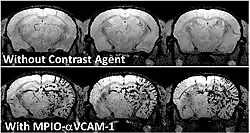

To achieve molecular imaging of disease biomarkers using MRI, targeted MRI contrast agents with high specificity and high relaxivity (sensitivity) are required. To date, many studies have been devoted to developing targeted-MRI contrast agents to achieve molecular imaging by MRI. Commonly, peptides, antibodies, or small ligands, and small protein domains, such as HER-2 affibodies, have been applied to achieve targeting. To enhance the sensitivity of the contrast agents, these targeting moieties are usually linked to high payload MRI contrast agents or MRI contrast agents with high relaxivities.[2] In particular, the recent development of micron-sized particles of iron oxide (MPIO) allowed to reach unprecedented levels of sensitivity to detect proteins expressed by arteries and veins.[3]